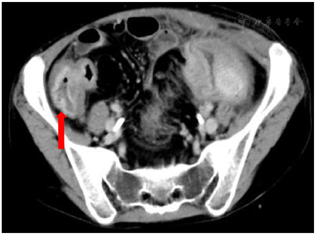

针对存在CD外科并发症(腹腔感染,肠梗阻)及营养不良的患者,需积极诱导疾病缓解,纠正营养不良,控制感染,为手术创造条件。治疗措施:(1)营养支持:患者存在肠梗阻、肠瘘及腹腔感染,缺乏有效的肠内营养通路,行肠外营养的同时积极尝试肠内营养,间接能量测定REE为876 kcal/d,实际能量需求为(1.2-1.5)×REE=1 051-1 314 kcal/d。通过放置肠梗阻导管建立有效的肠内营养通道(图3)。(2)控制腹腔感染:左下腹瘘口处置入黎氏双套管持续冲洗引流(图4)。